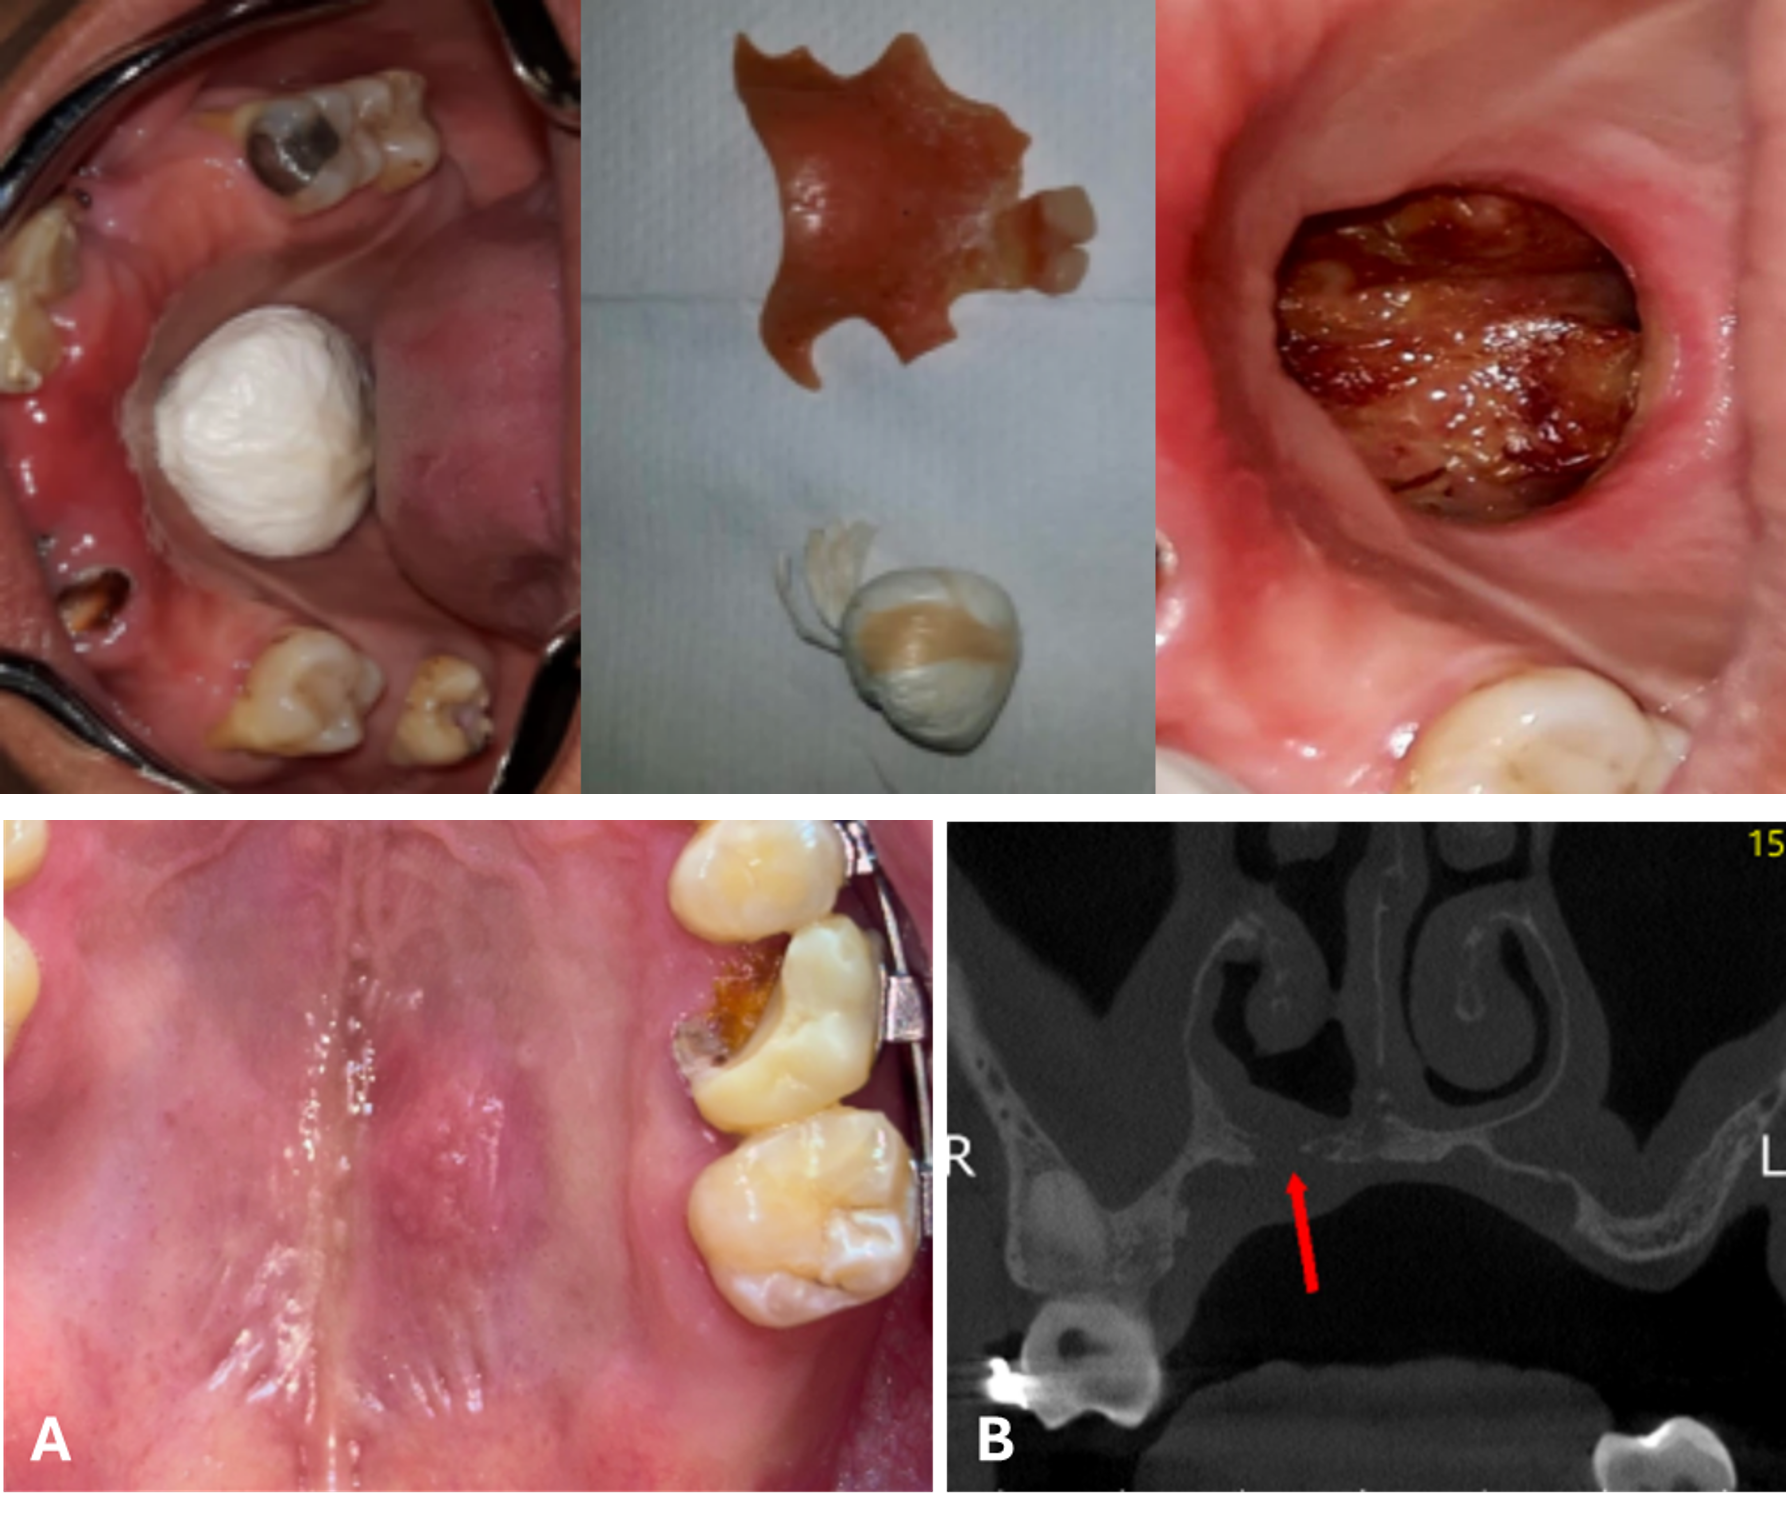

Osseointegration of a displaced dental implant in the maxillary sinus: a 7-year follow-up case report

Marcelo Rodrigues Azenha, Plauto Cristopher Aranha Watanabe, Sebastián Pérez Errázuriz, Luis Fernando Jardim, Ana Luisa Riul Sório